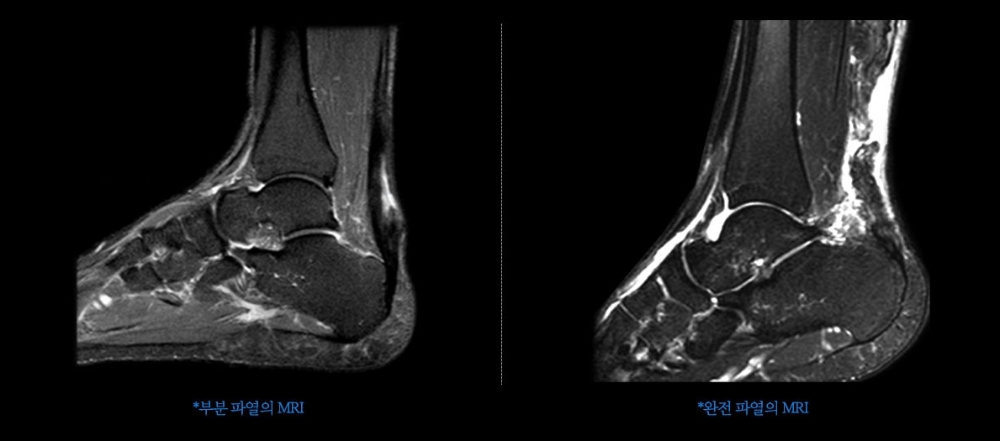

전문가들은 일반인이 축구를 함에 있어 가장 쉽게 부상을 당하는 부위는 발목이라고 말한다. 족부전문의인 연세건우병원 박의현 병원장은 “선수들처럼 근육이 발달되지도 않은 상태에서 공을 드리블하거나 상대 선수를 제치기 위해 페인트(눈속임) 동작을 하는 경우 발목 인대 부상 등을 입을 수 있다”고 설명한다. 또 “충분히 스트레칭을 하지 않은 상태에서 공을 차다가 아킬레스건이나 햄스트링 손상이 발생할 수도 있다”고 경고한다.